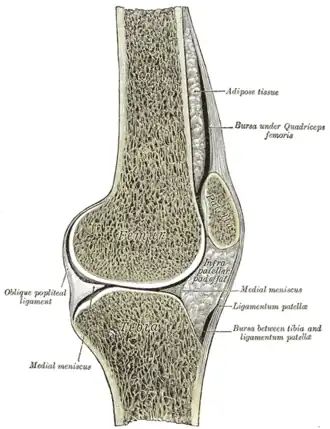

Сагиттальный разрез правого коленного сустава | |

Сесамовидные кости (от лат. Sesamum) — кости, расположенные в толще сухожилий и обычно лежащие на поверхности других костей. Сесамовидные кости отмечаются в областях, где сухожилия перекидываются через суставы (например, в области запястья, коленного сустава, стопы). Сесамовидные кости обеспечивают защиту сухожилий и удерживают сухожилия в некотором отдалении от центра сустава, увеличивая плечо силы.

Сесамовидные кости тесно связаны с капсулой сустава и сухожилиями мышц. Одна из поверхностей у них покрыта гиалиновым хрящом и обращена в полость сустава.

- коленный сустав — надколенник (в толще сухожилия четырёхглавой мышцы)